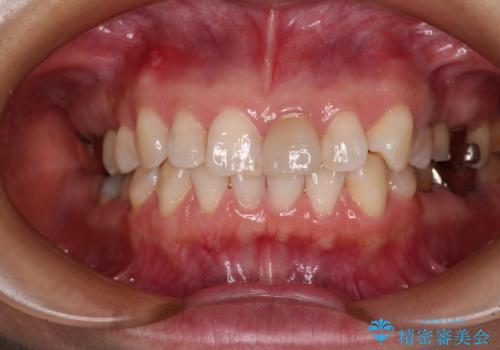

- 上下前歯のデコボコを気にして来院された患者様です。

カウンセリングにて詳しく話を聞いたところ、一番気になっているのは下顎前歯の叢生であり、上顎犬歯はあまり気になっていないとのことでした。

矯正治療は、歯の後戻りを抑制するために、治療終了後も保定装置をしっかりと使用していただくことが必須であるため、気になっている下顎だけを整えることで、その負担を半減できると考え、下顎のみの部分矯正として治療を行うこととしました。

装置としては、叢生の程度が強くなかったため、インビザラインの廉価版であるモデレート・パッケージを使用することとしました。